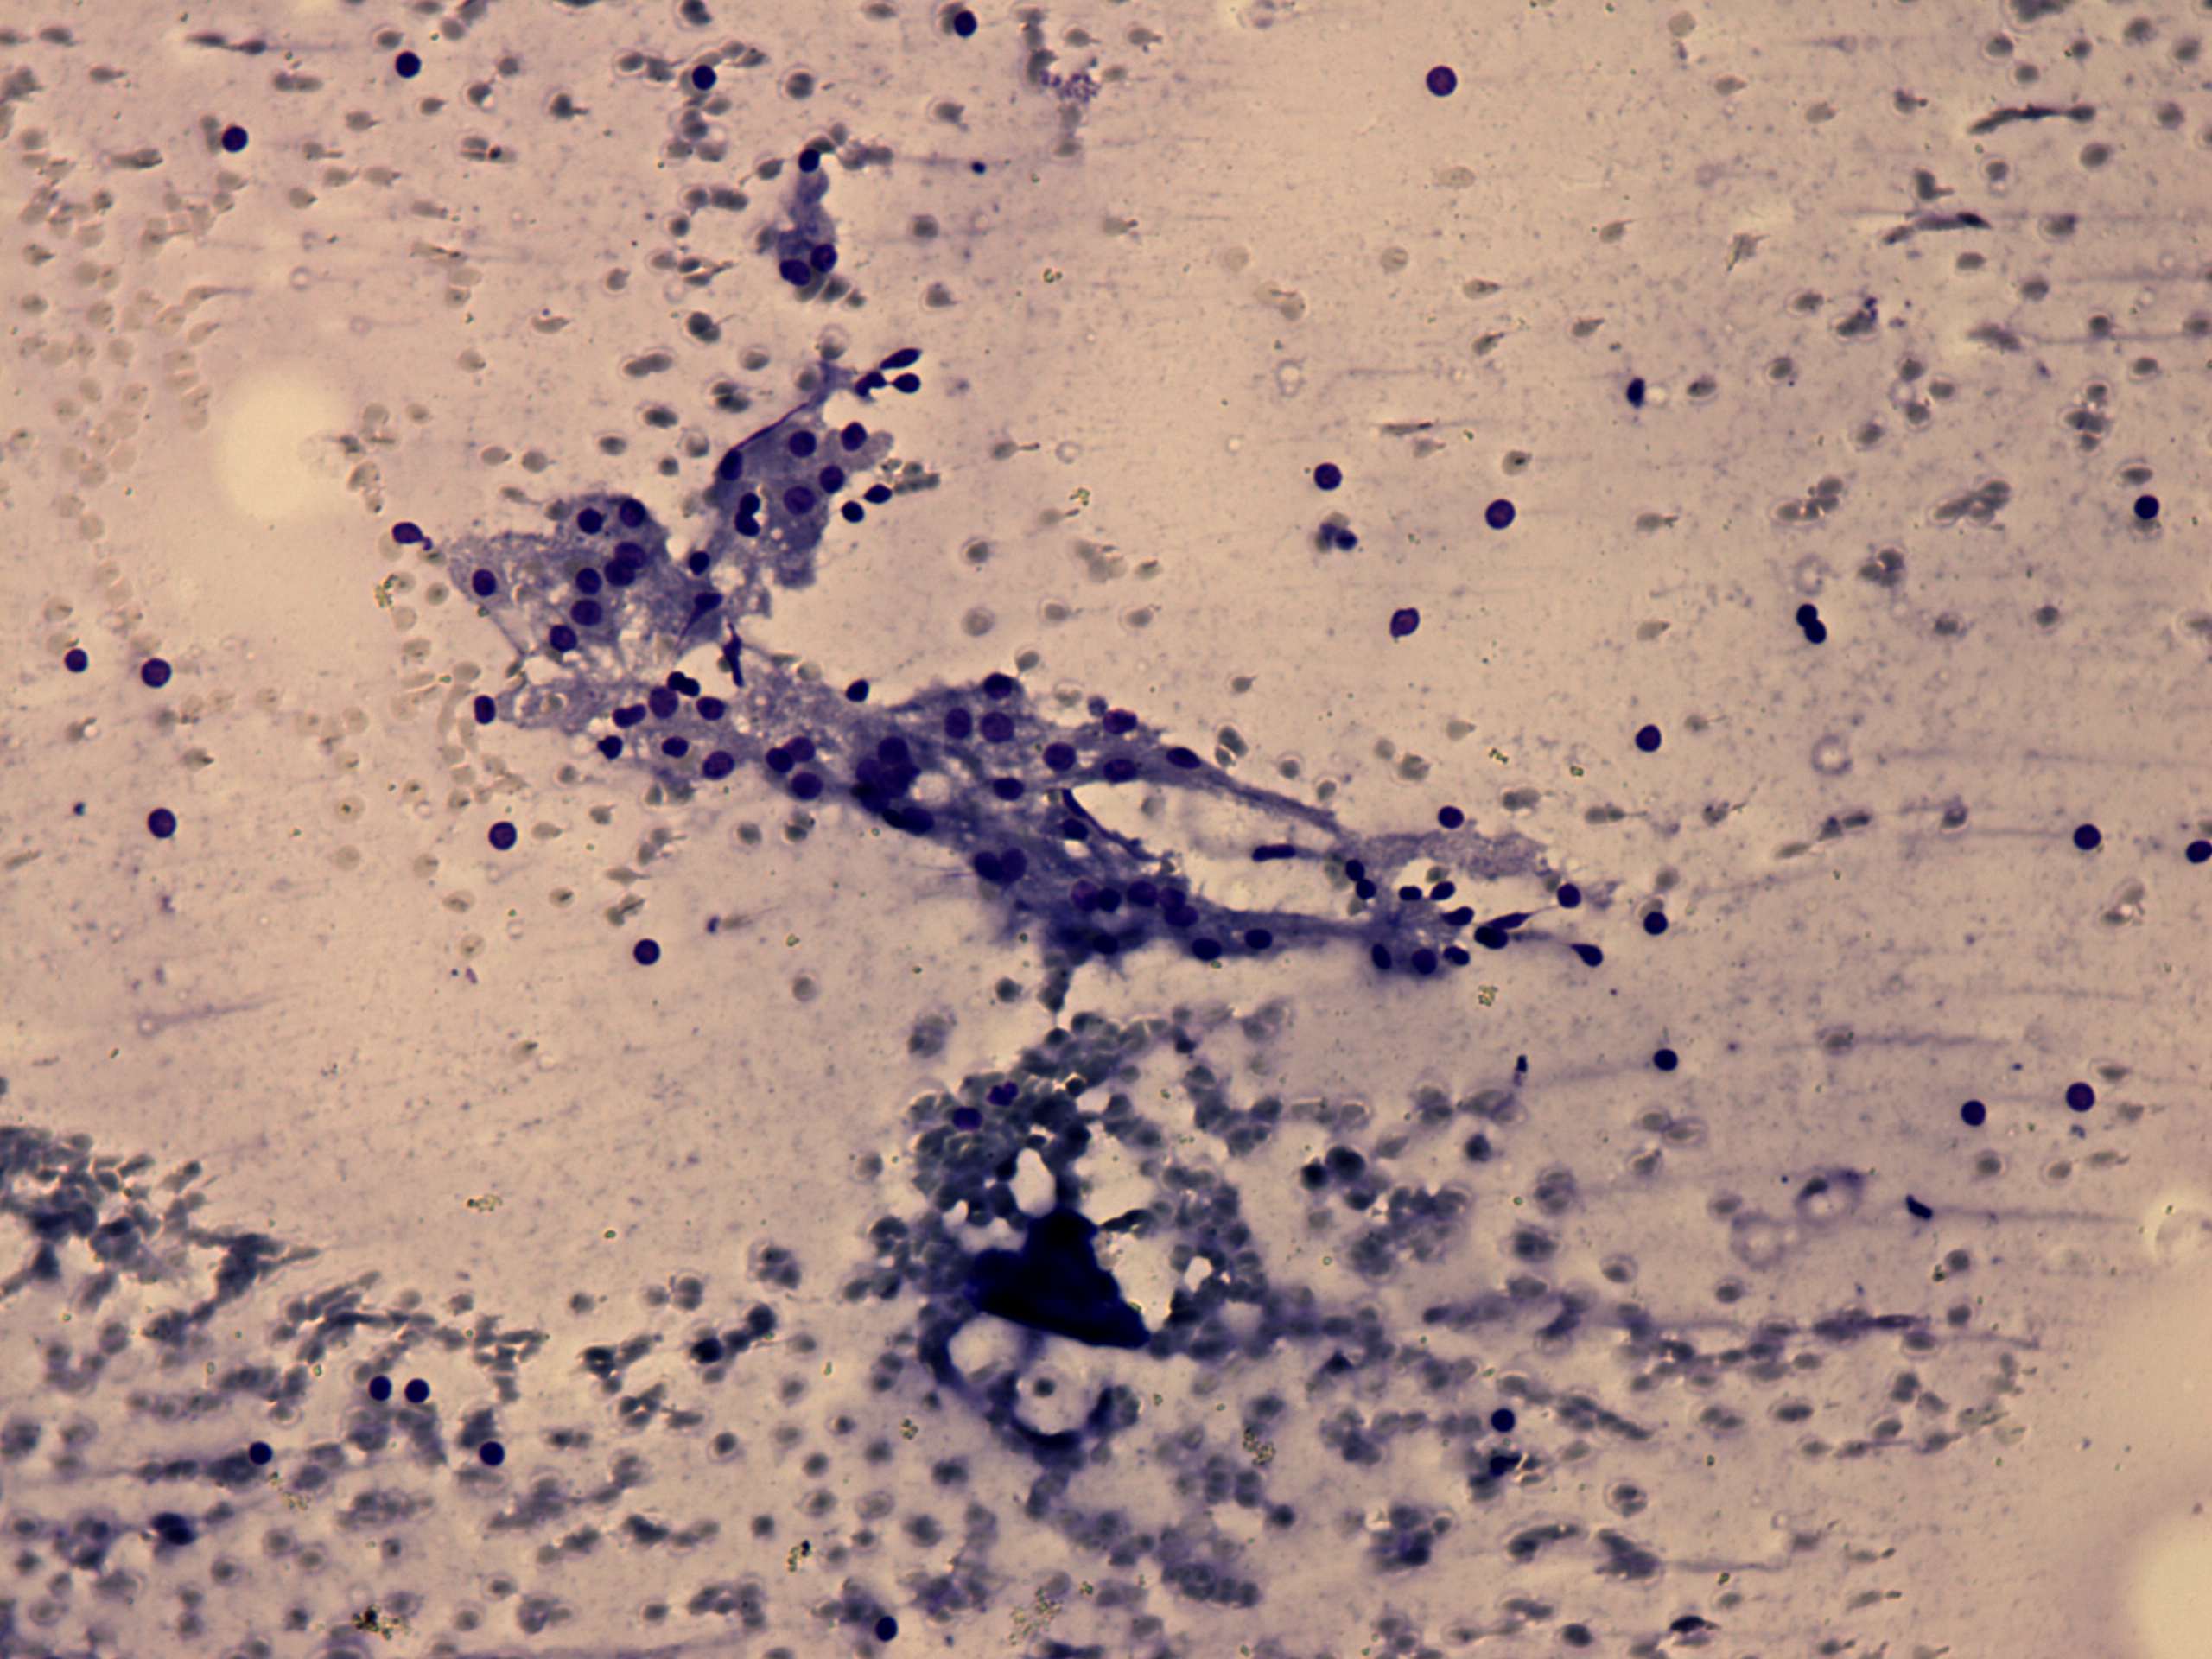

Parathyroid lesions - Case 2.

A patient with a multinodular goiter (cytologic picture 4)

Wright-Giemsa staining, 200x. Note vacuolization.